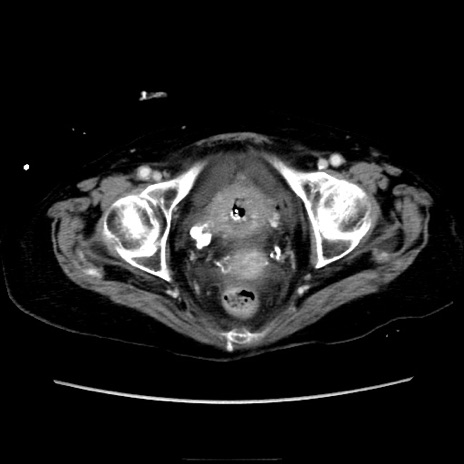

症例40(横断像)

【症例】90歳代女性

【主訴】腹痛・嘔吐

【現病歴】 食欲低下、嘔吐があり昨日他院受診。肺炎と診断され入院となる。入院後より腹部全体に圧痛あり。胃管留置され経過みていたが、症状持続するため、

当院転院となる。

【既往歴】胸椎圧迫骨折、胆石症

【身体所見】腹部:中央に激痛あり、圧痛あり、反跳痛不明

【データ】WBC 17100、CRP 18.82

横断像